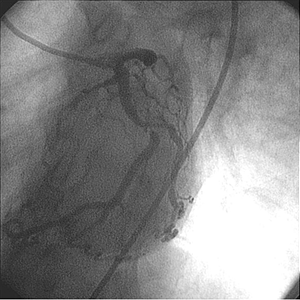

Diagnóstico

• La angiografía inicial mostró una arteria coronaria derecha pequeña no dominante

• La DA presentaba una enfermedad leve.

• La arteria circunfleja mostraba 90% de estenosis.

• La función ventricular izquierda era normal.